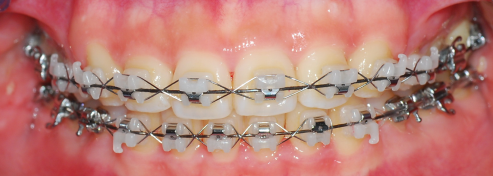

정면사진